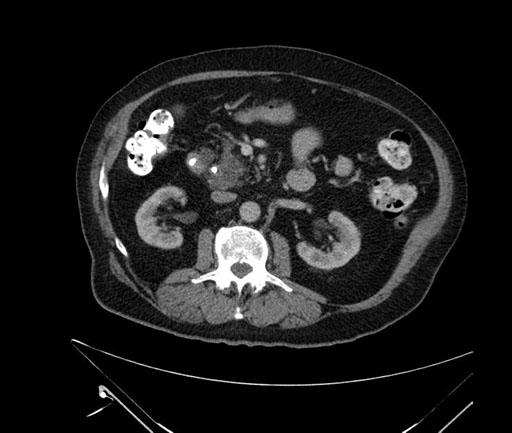

Imaging Analysis

Look through the patient's CT scan to identify any areas of concern for the necessary procedure.

Based on your CT findings, which issue(s) would give reason for "planned slowing down moment(s)" in this case?

Considering a standard Whipple procedure, what step(s) of the operation would you do differently in this case?